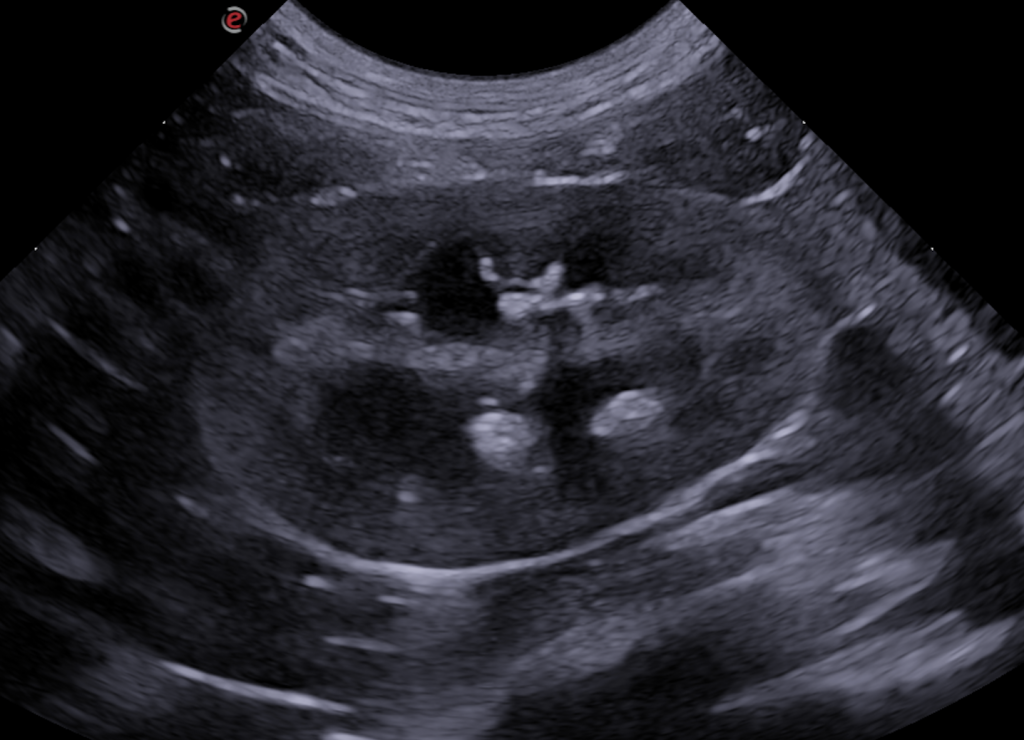

Ecografía abdominal:

- Ambos riñones presentan estructuras redondeadas, de 1-4 mm, con superficie hiperecogénica y sombra acústica distal asociada (cálculo), en los divertículos renales. Se observa una mínima distensión de la pelvis renal (2 mm)

- El ureter izquierdo está ligeramente distendido y presenta en todo su recorrido la pared engrosada, observándose aproximadamente a 4 cm de su inicio, una engrosamiento marcado de su pared de forma concéntrica y circunferencial, observándose una pared hipoecogénica de 2 mm de grosor. En su interior, hay una estructura similar a la descrito en ambos riñones (cálculo), de 1.7 mm de diámetro. El ureter distalmente disminuye abruptamente de tamaño y se continúa de forma normal hasta la unión ureterovesical. El peritoneo de alrededor del ureter se aprecia hiperecogénico en todo su recorrido.

- En la vejiga urinaria, se observó material ecogénico suspendido.

- El diagnóstico más probable fue una obstrucción ureteral parcial o crónica asociada a una cálculo, con formación de un granuloma ureteral asociado a una estrechez.